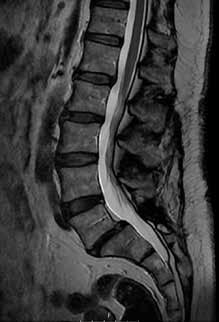

LANNERANGAN RYHTI on normaalisti edestä suora ja sivulta katsoen loivasti kaareva. Kaarevuuden eli lannenotkon suuruus vaihtelee, mutta kaikki lannerangan nikamat sijaitsevat normaalisti notkon muodostamalla jatkuvalla linjalla, jolloin ryhti on ehjä ja harmoninen. Nikamasiirtymä syntyy, kun joku nikamista siirtyy eteenpäin suhteessa alla olevaan nikamaan ja notkon harmonia häiriytyy. Siirtymästä käytetään kreikkalaisperäistä diagnoositermiä spondylolisteesi, jossa termin alkuosa spondylos viittaa nikamaan ja olisthesis siirtymään tai liukumaan.

Nikamasiirtymä on käytännössä aina sairausperäinen muutos. Suurin osa siirtymistä syntyy osana lannerangan kulumasairautta. Kuluma johtaa nikamien välisen rustoisen välilevyn madaltumiseen ja nikamien välisten pikkunivelten nivelrikkoon. Edelleenkään ei tarkoin ymmärretä, miksi tämä kehitys johtaa joskus nikaman siirtymiseen eteenpäin ja joskus vain nikamavälin madaltumiseen ilman siirtymää.

Tyypillinen paikka kulumaperäiselle siirtymälle on lannerangan toiseksi alin L4/5-väli, ja on ajateltu joidenkin paikallisten anatomiaan liittyvien tekijöiden voivan selittää siirtymän syntyä (kuva 1A). Tiedetään myös, että kulumaperäinen siirtymä on naisilla yleisempi kuin miehillä eli jokin sukupuoleen liittyvä selittävä tekijäkin on olemassa.

Lannerangan kulumasairaus kehittyy iän myötä ja vastaavasti kulumaperäistä siirtymää tavataan vanhemmalla väestöllä. Yli 65-vuotiailla siirtymän esiintyvyys on jopa 25 prosenttia eli joka neljännellä tämän ikäisellä ihmisellä on nikamasiirtymä.

Kuva 1. Magneettikuvat lannerangasta seisovassa asennossa sivusuunnasta katsottuna. Kuvassa A näkyy L4-nikaman kulumaperäinen siirtymä eteenpäin (nuoli). Välilevy nikamasiirtymän kohdalla on madaltunut kulumamuutoksena. Kuvassa B näkyy rasitusmurtuman pohjalta syntynyt nikamasiirtymä L5-nikamassa (nuoli). Myös tässä siirtymävälin välilevy on madaltunut kuluman seurauksena.